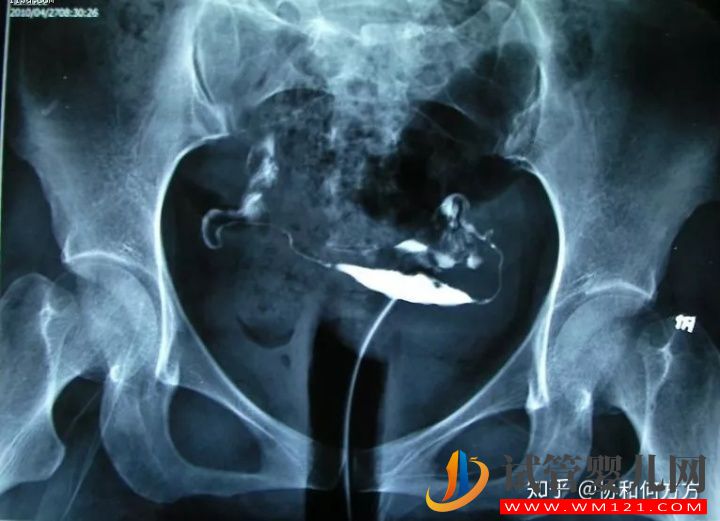

5 輸卵管積水

造影片的表現(xiàn)是一側(cè)或雙側(cè)輸卵管遠(yuǎn)端增粗、膨大,呈“臘腸狀”。這是由于輸卵管遠(yuǎn)端粘連不通導(dǎo)致輸卵管內(nèi)造影劑不能溢出所導(dǎo)致。所以,輸卵管積水的前提是輸卵管不通。如果造影片顯示輸卵管傘端有造影劑溢出就不是積水。輸卵管積水會影響試管嬰兒的成功率,建議在胚胎移植前先處理輸卵管積水。

輸卵管積水